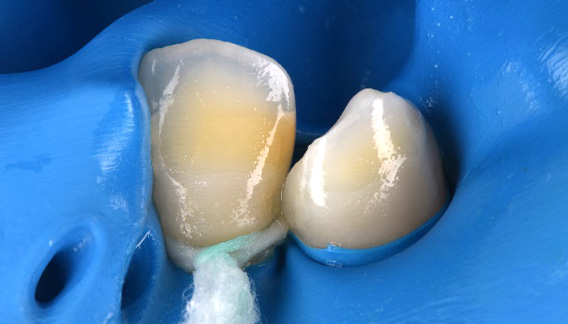

| 院長コメント | ①むし歯を治療して歯を型どりする時 ②ジルコニアを歯と接着させる時 唾液を極力排除する必要があります。ラバーダムというゴムの膜を用いて歯を唾液から隔離します。今回はかぶせ物(クラウン)の形で接着面全周をラバーダムの上に出すのはかなり難しかったのですが、工夫をすることで接着面全てをラバーダムの上に設置することができ、接着力を最大限に発揮できました。 |